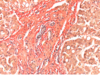

chron. Blutstauung der Leber (vG)

- Hyperämie und Dilatation der läppchenzentralen Sinus mit Bildung von Stauungstrassen

- perisinusoidale Kollagenfaserbildung (rot)

- Druckatrophie der Leberzellbalken, abschnittsweise bis zum vollständigen Schwund

- Ersatz durch streifenförmige Fibrose